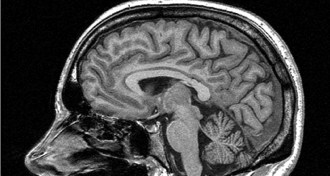

Ways of seeing the brain inspire notions of how it works

As scientists have developed more sophisticated methods and ideas, their understanding of how the brain works has shifted too.